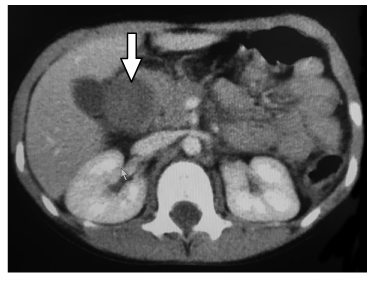

Se le realizaron exámenes de laboratorio que dieron como resultado una alcalosis metabólica, un aumento de los glóbulos blancos (90% polimorfonucleares), amilasa elevada (236 UI/L) y lipasa también alta (140 UI/L). La ecografía abdominal mostró una imagen ovoidea bien delimitada, hipoecoica de 50 x 26 x 26 mm de tamaño, con una ecotextura heterogénea y sin vascularización en la exploración Doppler, compatible con un hematoma de la segunda porción del duodeno (Figura 1). Esto se confirmó mediante una tomografía axial computarizada con y sin contraste intravenoso, estableciendo la ubicación no solo en la segunda, sino también en la tercera porción del duodeno y de un diámetro de 50 mm (Figura 2).

Es fundamental utilizar las técnicas de imagen como la ecografía y la tomografía computarizada para establecer el diagnóstico.3, 8,9 En el caso presentado, la tomografía no solo confirmó la presencia del hematoma que se muestra en la ecografía, sino que también proporcionó nuevos datos sobre el tamaño y la ubicación.